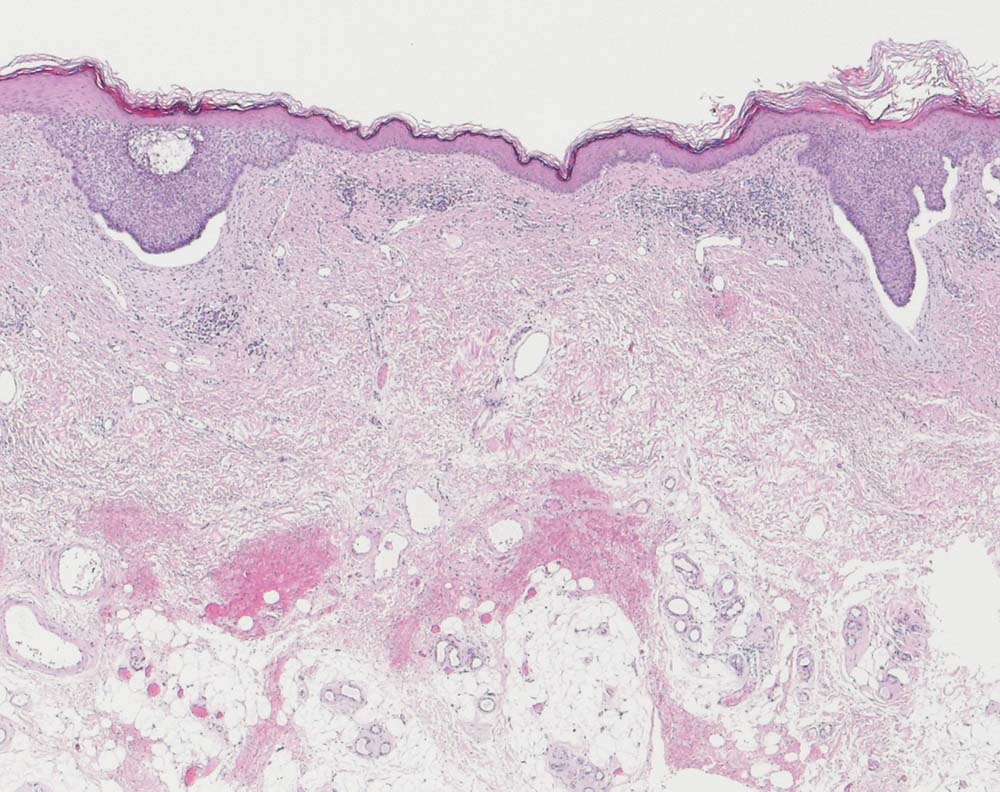

Oberflächlich multizentrisches Basalzellkarzinom

Von der Epidermis ausgehende basaloide Zellnester mit peripherer Palisadierung und charakteristischem Retraktionsartefakt zwischen Tumorzellen und angrenzendem Stroma. Zwischen beiden Zellnestern ist die Haut tumorfrei.

Basaliom Axilla.

Histologie

25